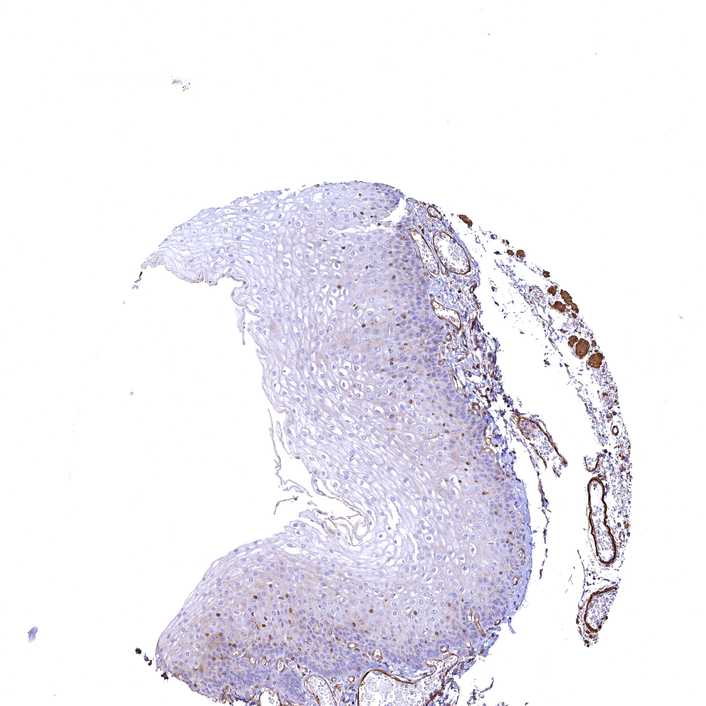

ESOPHAGUS - Antibody stainingi

Antibody staining in the annotated cell types in the current human tissue is reported as not detected, low, medium, or high, based on conventional immunohistochemistry profiling in selected tissues. This score is based on the combination of the staining intensity and fraction of stained cells.

Each image is clickable and will lead to virtual microscopy that enables deeper exploration of all samples and also displays staining intensity scores, fraction scores and subcellular localization as well as patient and tissue information for each sample.

Antibody CAB033678

Squamous epithelial cells Low